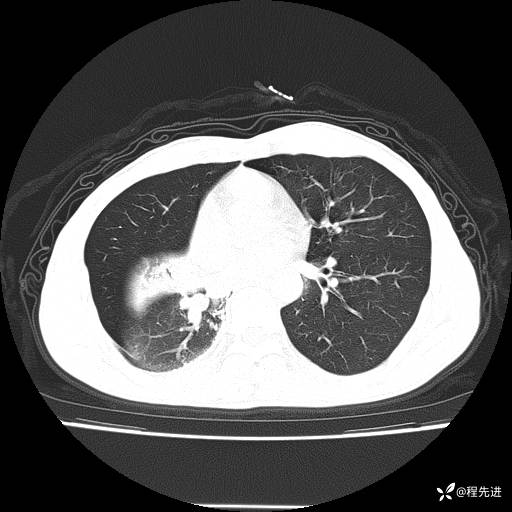

患者性别:男

患者年龄:49岁

主诉:咳嗽、胸痛1周

简要病史:1周前受凉感冒后开始出现咳嗽症状,阵发性连声咳,痰多,黄白痰,不易咳出,伴胸痛、气紧、胸闷,右侧为主,活动用力、呼吸时胸痛明显,曾在当地诊所贴敷膏药仍疼痛

体格检查:T:36.3 ℃ P:80 次/分 R:20 次/分 BP:120/88 mmHg,指脉氧饱和度97%,意识清晰,呼吸平稳,右侧第二、三肋骨压痛,可见膏药贴敷,皮肤无异常,双肺呼吸音粗,未闻及干湿性啰音。心率80次/分,节律整齐,无杂音。腹平软,全腹无压痛无反跳痛

临床诊断:社区获得性肺炎

CT平扫: